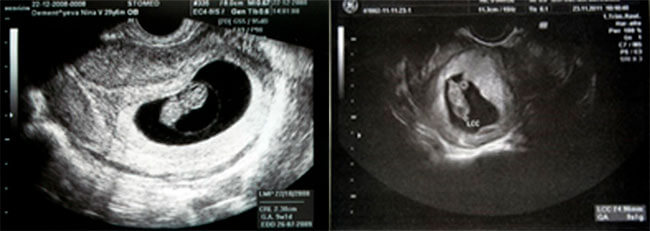

5-6 hepdelik düwünçek USB şeýle şekilde görünýär:

5-6 hepdelik embrionsyz tohum ýumurtgasy bolsa şeýle görünýär: